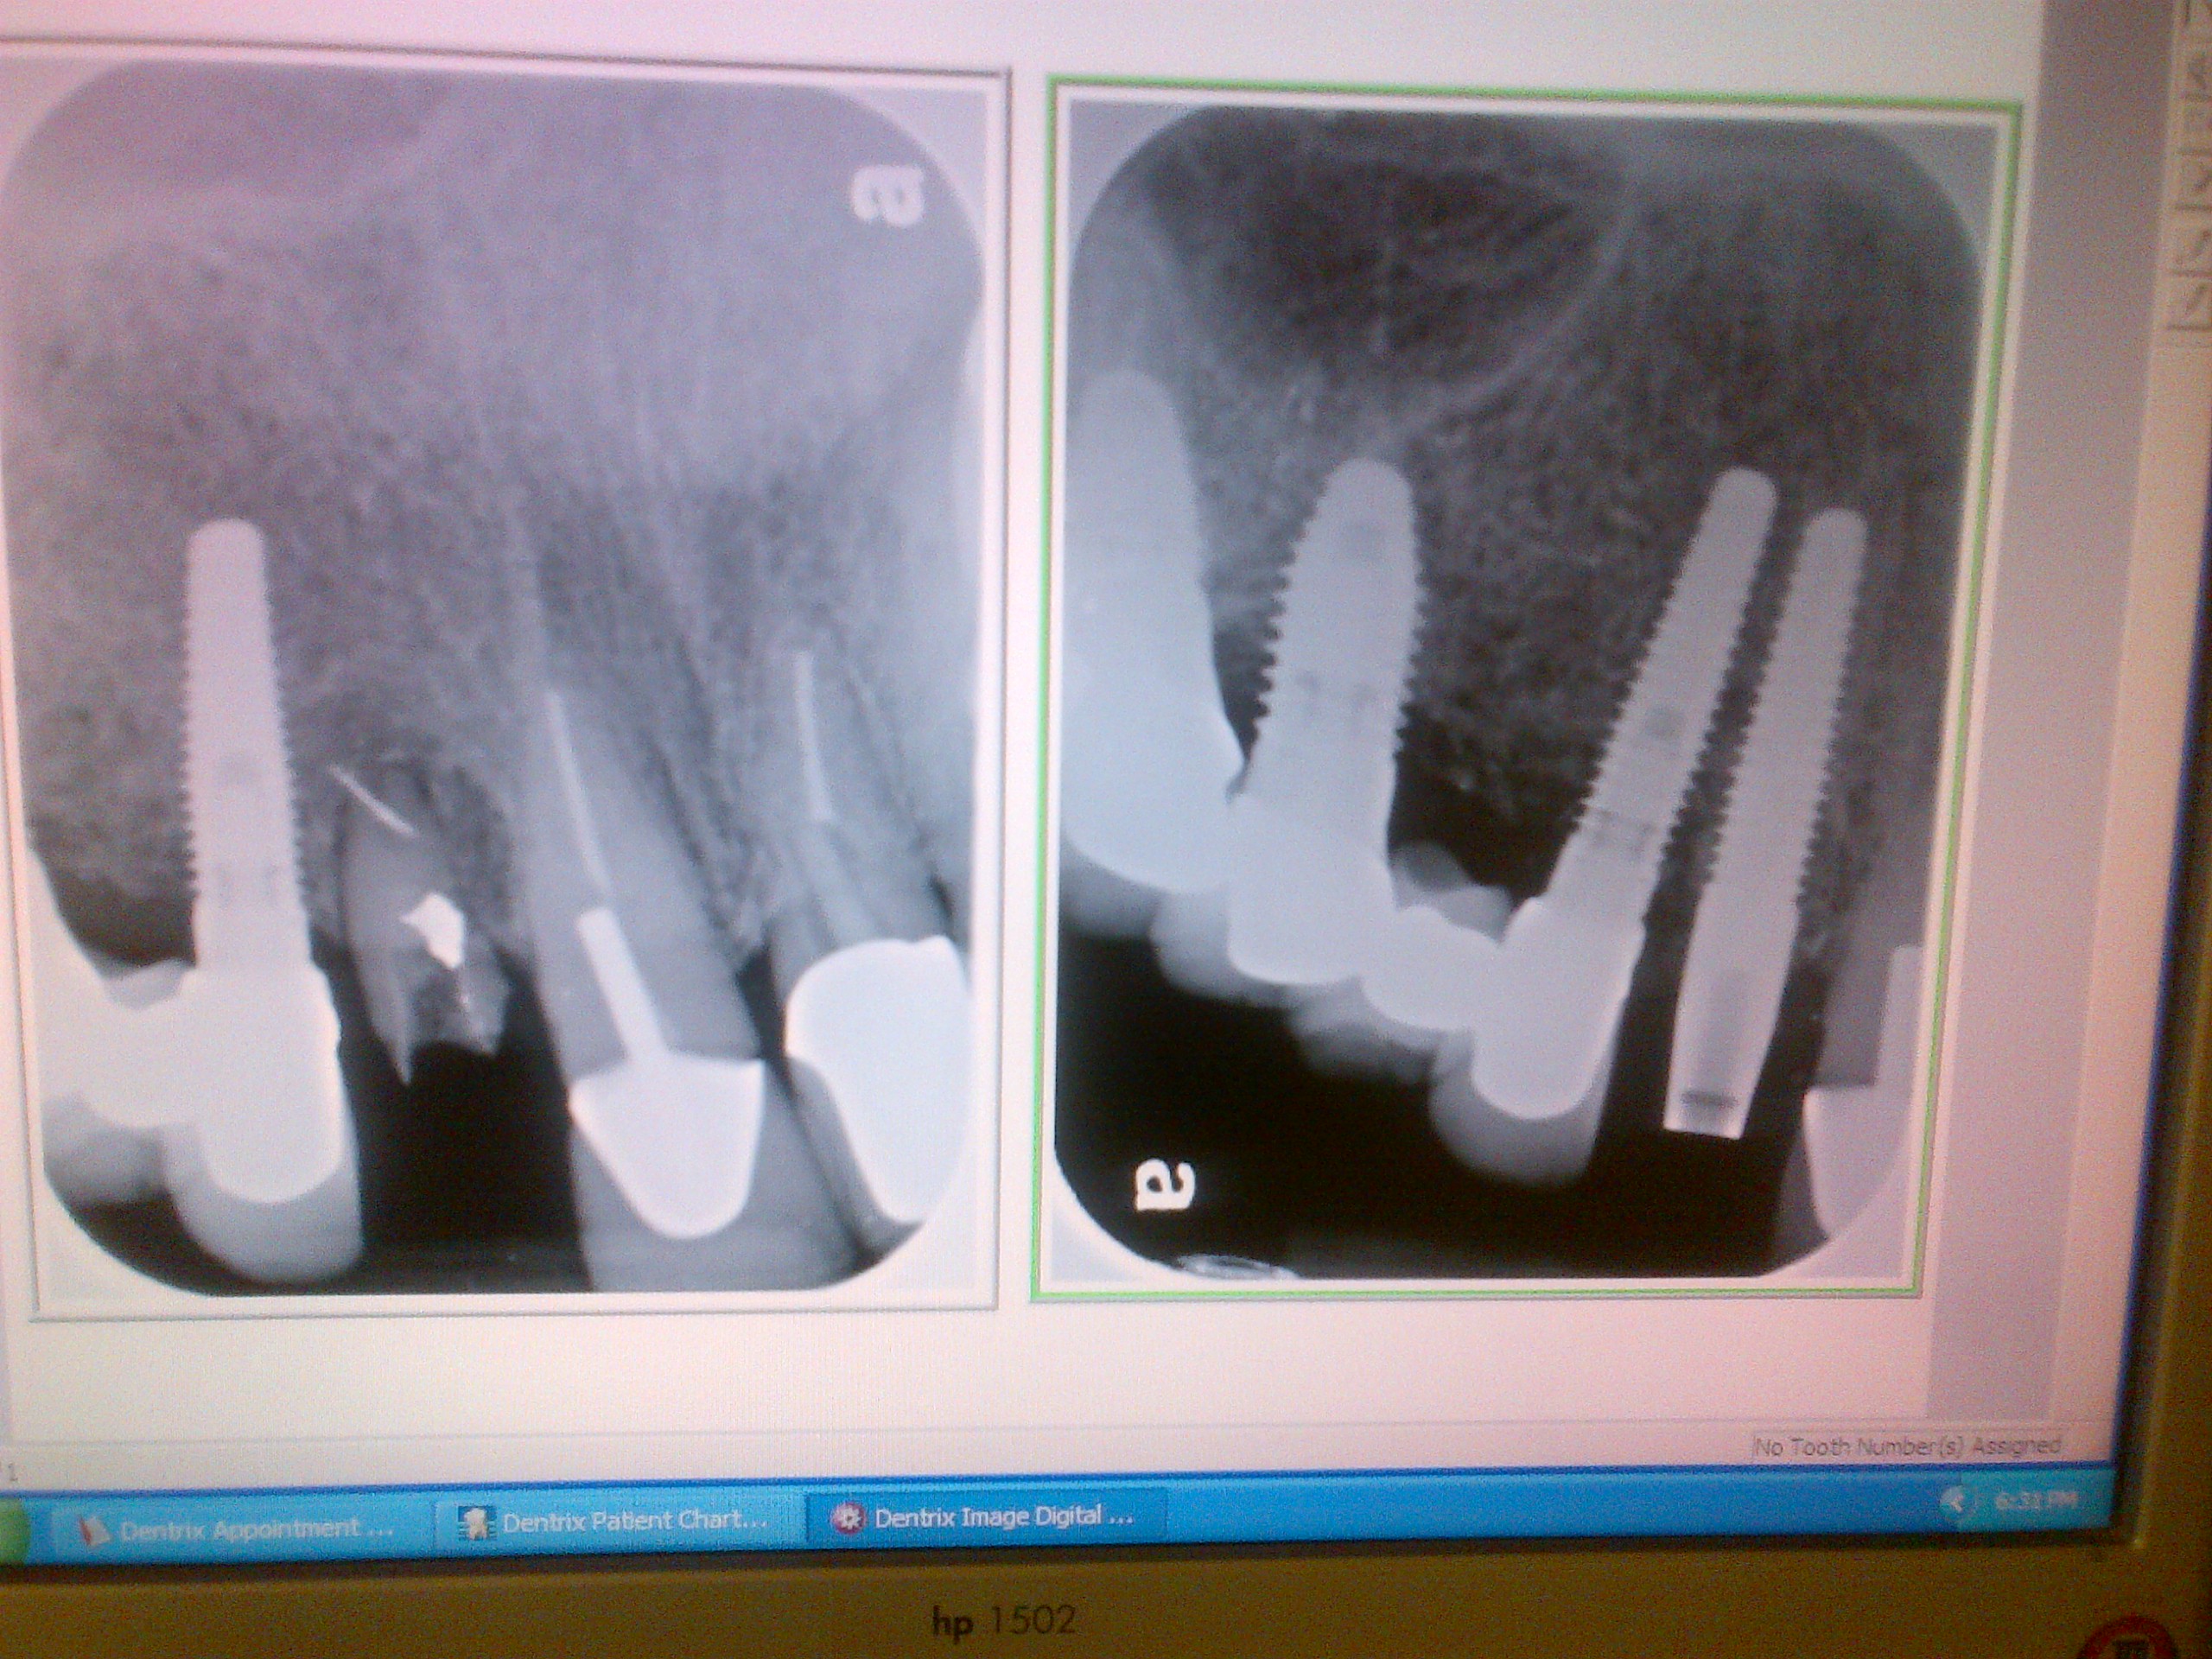

Left photo:  Patient presents as a same day  emergency; post/core crown #7 broken off.

Right photo:  #7 fractured root was extracted, a Nobel Biocare one-piece implant was placed with bone grafting.

The one piece implant allows for an immediate temporary acrylic crown.

Left:  Fractured tooth root - apical 1/3 near sinus     |    Right: Tooth extraction and immediate Implant placement